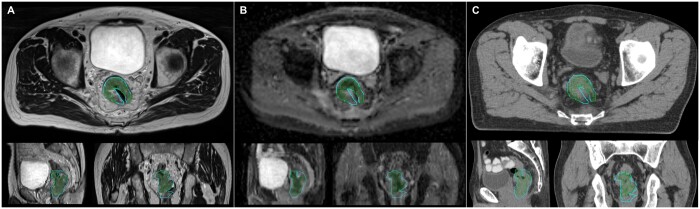

Methods: Ten patients previously treated with curative-intent standard long-course radiotherapy (50 Gy/25#) were re-planned. Boost target volumes (BTVs) were delineated semi-automatically using 40th centile intra-tumoural apparent diffusion coefficient value with expansions (anteroposterior 11 mm, transverse 7 mm, craniocaudal 13 mm). Biased-dosed combined plans consisted of a single-fraction volumetric modulated arc therapy flattening-filter-free (VMAT-FFF) boost (phase 1) of 5, 7, or 10 Gy before long-course VMAT (phase 2). Phase 1 plans were assessed with reference to stereotactic conformality and deliverability measures. Combined plans were evaluated with reference to standard long-course therapy dose constraints.

Abstract Image